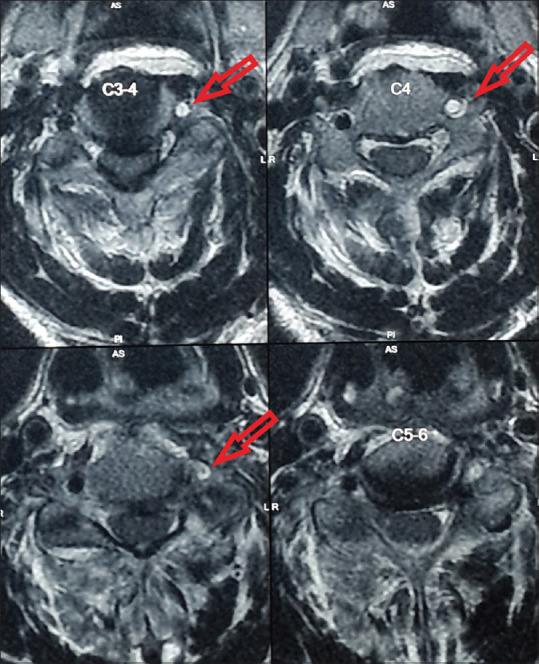

MATERIALS AND METHODS

This was a single-center prospective study performed on 61 patients using plain magnetic resonance imaging (MRI) as a screening tool to assess the frequency of VAI and routine X-ray to detect morphological fracture patterns associated with the VAI in posttraumatic cervical spine cases. If the MRI study showed any evidence of vascular disruption, then further investigation in the form of computed tomography angiography was done to confirm the diagnosis.

This study showed the incidence of VAI was 14.75% (9/61). Of 61 patients, 16 had supraaxial, and 45 patients sustained subaxial cervical spine fractures. In the cohort of nine cases of VAI, eight patients had subaxial cervical spine injuries, of which seven were due to flexion-distraction injury. C5-C6 flexion-distraction injury was most commonly associated with VAI (4 cases). Of the nine cases, five succumbed to injury (mortality 55.55%), and 19 patients from the non-VAI group succumbed to injury (mortality 36.53%). From surviving four cases with VAI, two had improvement in the American Spinal Injury Association scale by Grade 1.

材料与方法

这是一项单中心前瞻性研究,对61例患者进行了研究,使用普通磁共振成像(MRI)作为筛查工具来评估VAI的发生率,并使用常规X线检查来检测创伤后颈椎病例中与VAI相关的形态学骨折模式。如果MRI检查显示有任何血管中断的迹象,则以计算机断层血管造影的形式进行进一步检查以确诊。

本研究显示VAI的发生率为14.75%(9/61)。61例患者中,16例为轴上骨折,45例为轴下颈椎骨折。在9例VAI病例组中,8例患者有轴下颈椎损伤,其中7例是由于屈曲-牵张损伤。C5-C6屈曲-牵张损伤最常与VAI相关(4例)。9例病例中,5例死亡(死亡率55.55%),非VAI组的19例患者死亡(死亡率36.53%)。在4例存活的VAI病例中,2例美国脊髓损伤协会评分提高了1级。